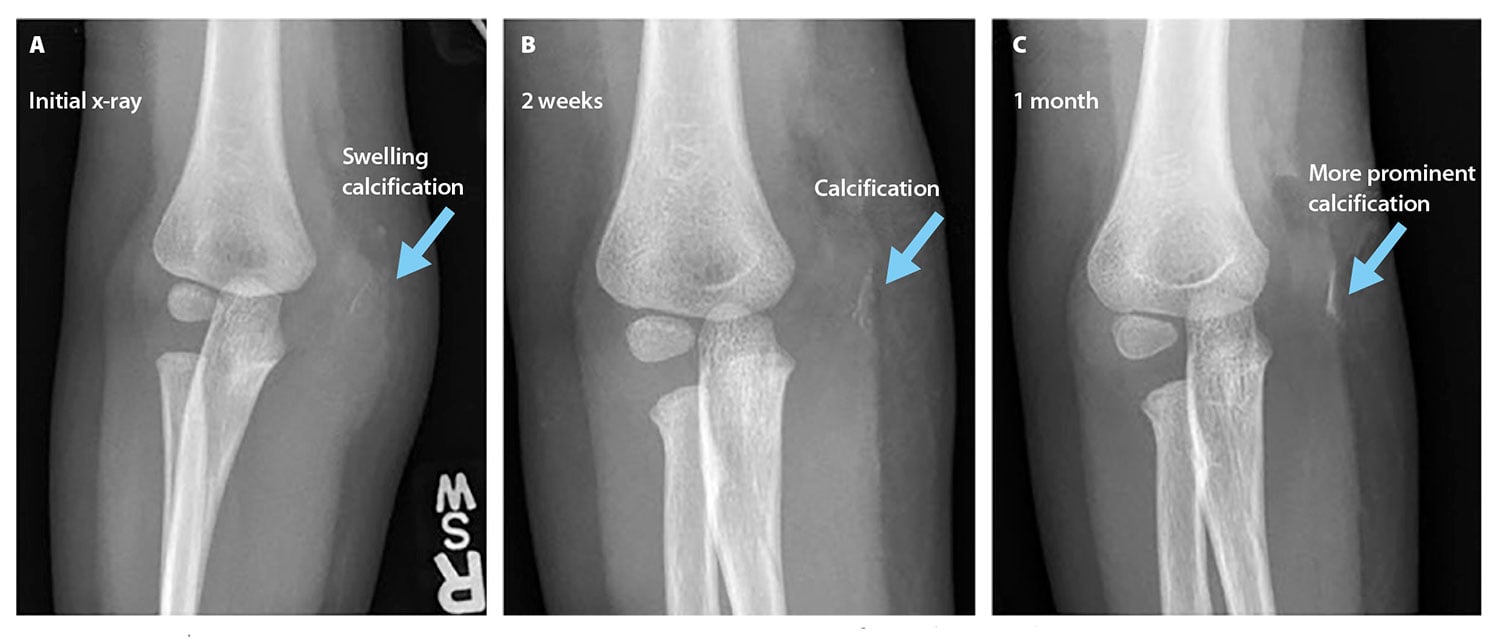

A 2-year-old child presented to the emergency department with right elbow pain after falling off a bench at school. The emergency department physician noted swelling around the medial condyle and decreased range of motion. A radiograph of the injured elbow revealed evidence of soft-tissue swelling but no fracture (see Figure 2). The patient was discharged and instructed to wear a sling for 1 to 2 weeks and to follow up with the orthopedics department.

At a follow-up appointment with the orthopedics department, the patient continued to exhibit pain and swelling in the right elbow, as well as an inability to straighten the elbow and a refusal to use the right arm. A radiograph revealed decreased soft-tissue swelling and a posterior fat pad, not previously observed, that indicated possible joint effusion. The radiograph also revealed a calcification in the area of the swelling (see Figure 2). These findings indicated a possible fracture, and the patient’s right elbow was placed in a cast for 2 weeks.

Figure 2. Radiographs obtained in the anterioposterior views in sequential order. A. First radiograph obtained showing soft-tissue swelling. B. Follow-up radiograph showing suspicious calcification in area of injury. C. Postcast radiograph showing increased prominence of calcification, indi- cating possible medial epicondyle and condyle avulsion fracture. Images courtesy of the authors.

After the cast was removed, swelling and limited range of motion still were present in the elbow. Another radiograph showed an ossified structure overlying the medial joint and a periosteal reaction along the distal dorsal cortex of the right humerus. The findings raised the possibility of a medial epicondylar avulsion fracture, and an MR examination was ordered to evaluate the area.